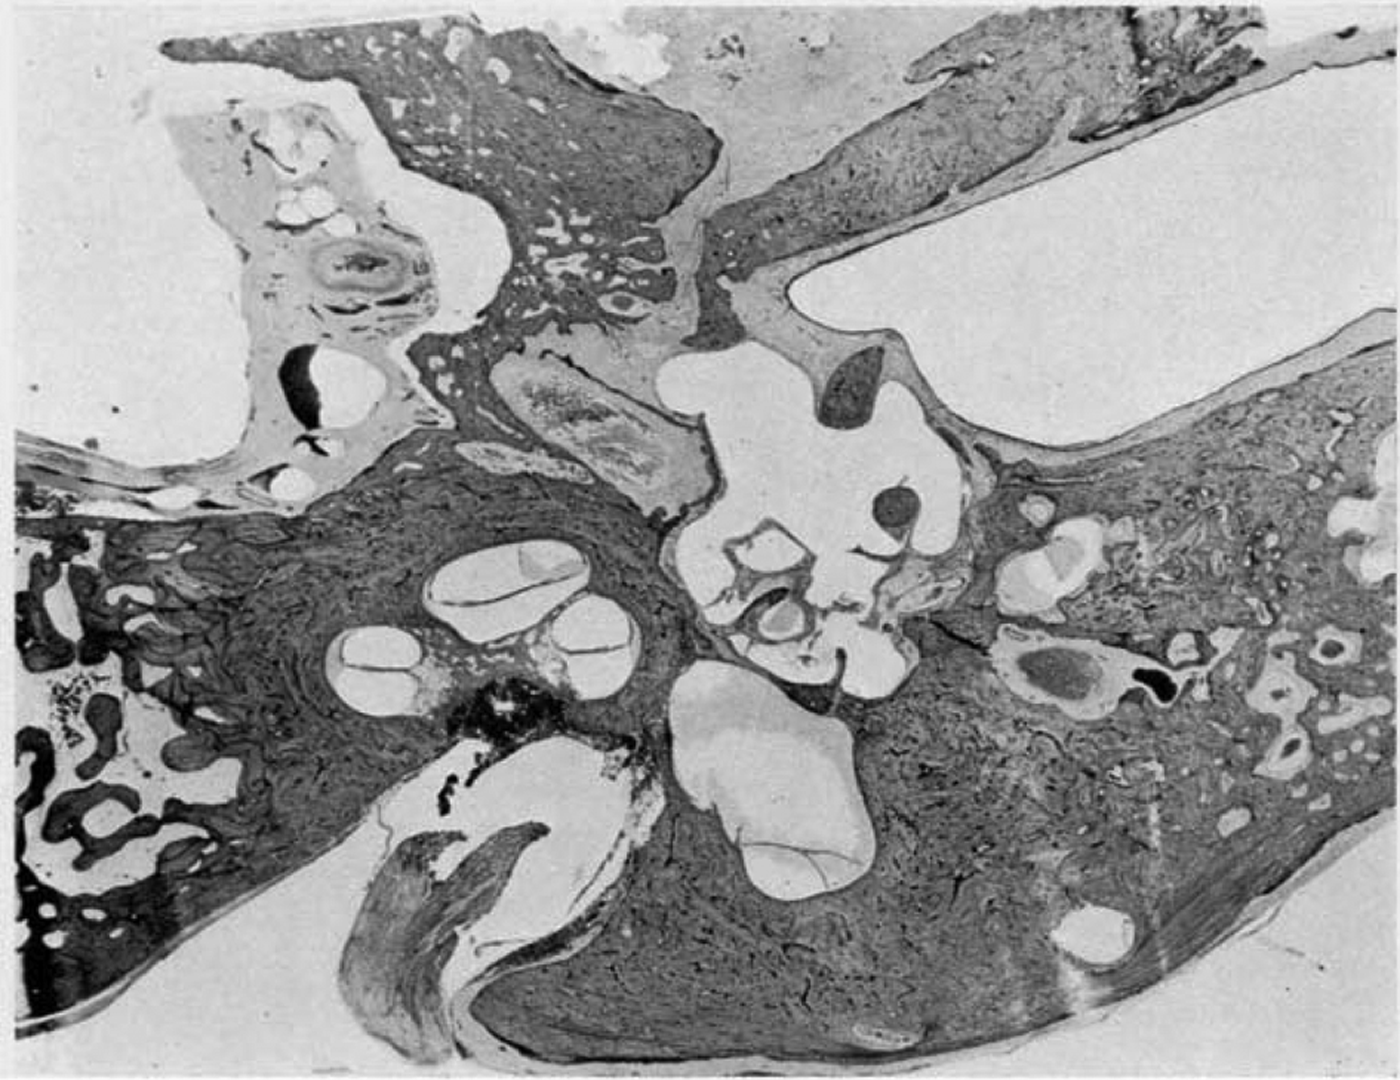

The vestibule.—There is a gross dilatation of the endolymph spaces, in particular of the saccule [Figure 3]. At the level of the stapes footplate the saccule extends around the lateral aspect of the utricle to enclose it on its posterior aspect and extends into the inner extremity of the lateral semi-circular canal. The perilymph cistern has been obliterated.

There is a gross dilatation of the endolymph system which affects chiefly the scala media of the cochlea and the saccule.

Fig. 3 ‘Case I. Left temporal bone. Low power view showing chronic inflammatory changes within the tympanum, and gross dilatation of the endolymph spaces of the vestibule and the cochlea.’Reference Hallpike and Cairns11